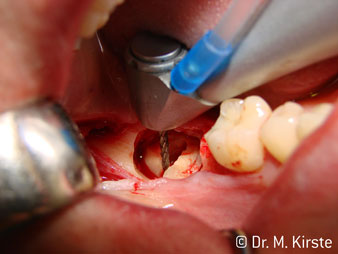

Elegir el ángulo de 45º ofrece múltiples ventajas de uso. Los odontólogos dedicados a cirugía (para quienes se desarrolló principalmente esta pieza de mano) se percatarán de inmediato de que se puede trabajar de forma muy específica. En especial en la remoción de las muelas del juicio (Fig. 2), no es necesaria una gran abducción de las partes blandas en la zona del carrillo (Fig. 3). El diseño del cabezal de la pieza de mano, combinado con los suaves giros del cabezal durante la preparación, permite trabajar de forma rápida y segura en la zona retromolar.

El nuevo diseño de los rodamientos dentro del cabezal de la pieza de mano garantiza el funcionamiento silencioso de la fresa, en la separación del diente o la raíz (Fig. 4-9) se muestra una impresionante imagen de corte sin efectos de impacto.